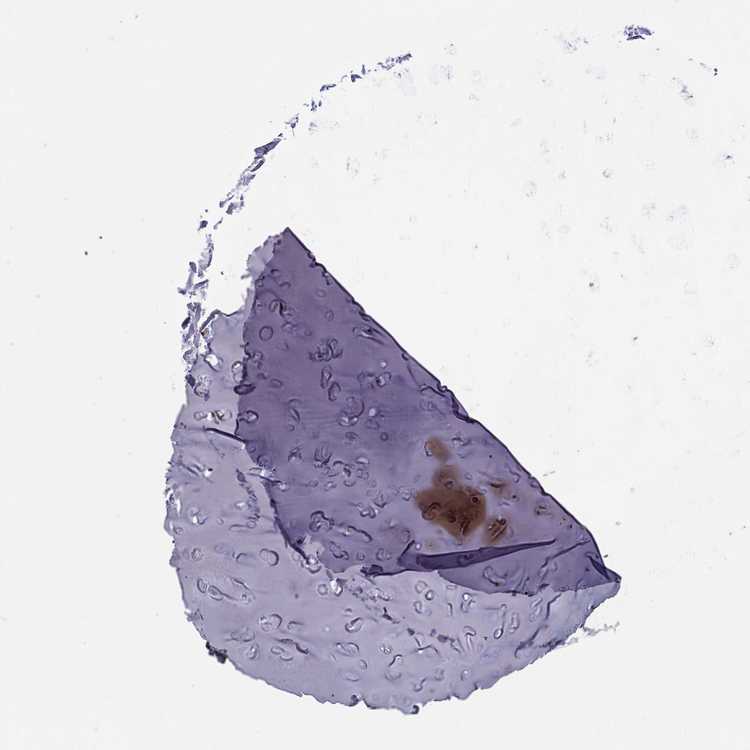

SOFT TISSUE 1 - Antibody stainingi

Antibody staining in the annotated cell types in the current human tissue is reported as not detected, low, medium, or high, based on conventional immunohistochemistry profiling in selected tissues. This score is based on the combination of the staining intensity and fraction of stained cells.

Each image is clickable and will lead to virtual microscopy that enables deeper exploration of all samples and also displays staining intensity scores, fraction scores and subcellular localization as well as patient and tissue information for each sample.

Antibody HPA051937

Chondrocytes Medium

Fibroblasts Medium

SOFT TISSUE 2 - Antibody stainingi

Peripheral nerve Medium